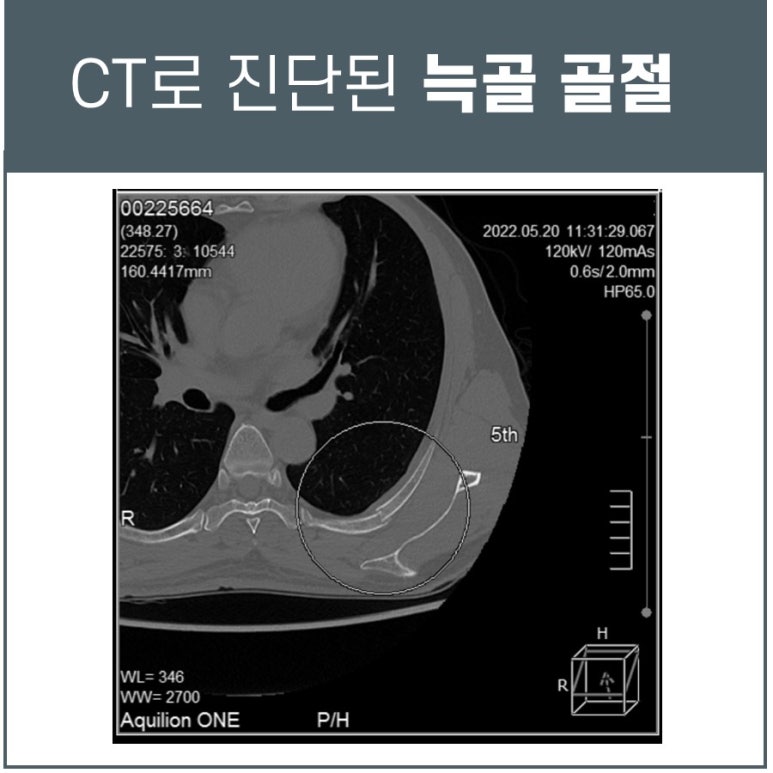

늑골 골절의 CT 진단

자전거 타다가 앞으로 넘어진 후 옆구리~날개뼈 통증으로 오신 50대 남성분입니다.

타 한의원에서 치료를 받았으나 그 때만 괜찮고 다시 아프다고 하시는데요. 늑골 골절이 의심되어 인근 영상의학과로 전원하여 CT검사를 진행한 결과, 제4/5/6/7번 늑골의 골절, 앞과 뒤를 합쳐서 총 7부위의 골절로 진단되었습니다.